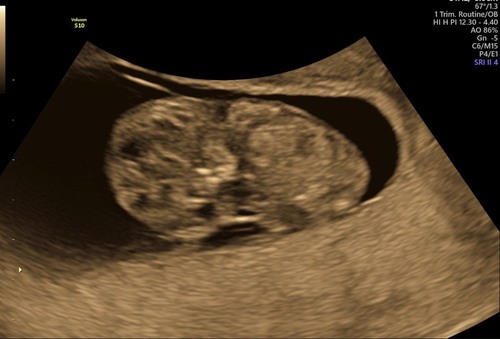

Hallo dames, even een update. Baby doet het goed! Alleen liet hij of zij zich niet helemaal zien haha dus ik mag volgende week opnieuw komen voor de meting etc van de termijn echo. Ben dan 11 weken hopelijk, heb niet de beste echo foto’s maar voor mij wel heel bijzonder. Bruine afscheiding dus dagen na sex is normaal! Het lijkt bijna klaar te zijn. Hopelijk snel.🥰